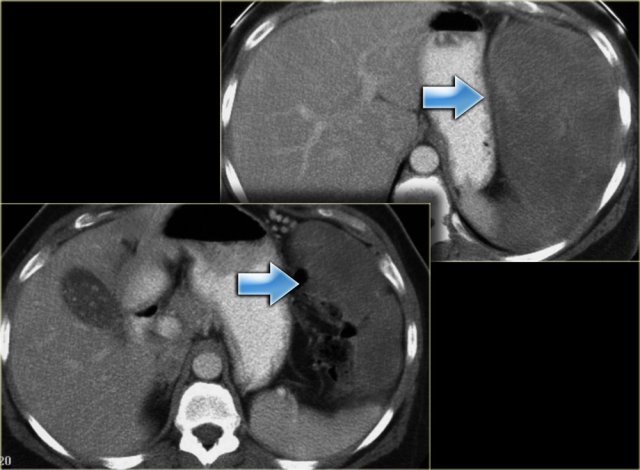

Mesenteric fibromatosis - Desmoid (3)

On the left again a more typical case with a low density tumor located in the greater omentum (upper image) and the gastrosplenic ligament (lower image).

On the left an unusual location, because normally there is no mesentery deep in the pelvis.

This patient had familial adenomatous polyposis.

A total colectomy with J-pouch of the ileum was performed.

Now accompanying that J-pouch is mesentery in which mesenteric fibromatosis has developed.

Notice the low attenuation foci or bands of myxoid stroma within the tumor.

In familial adenomatous polyposis the mesenteric fibromatosis is almost always post operative and occurs at the operative sites.